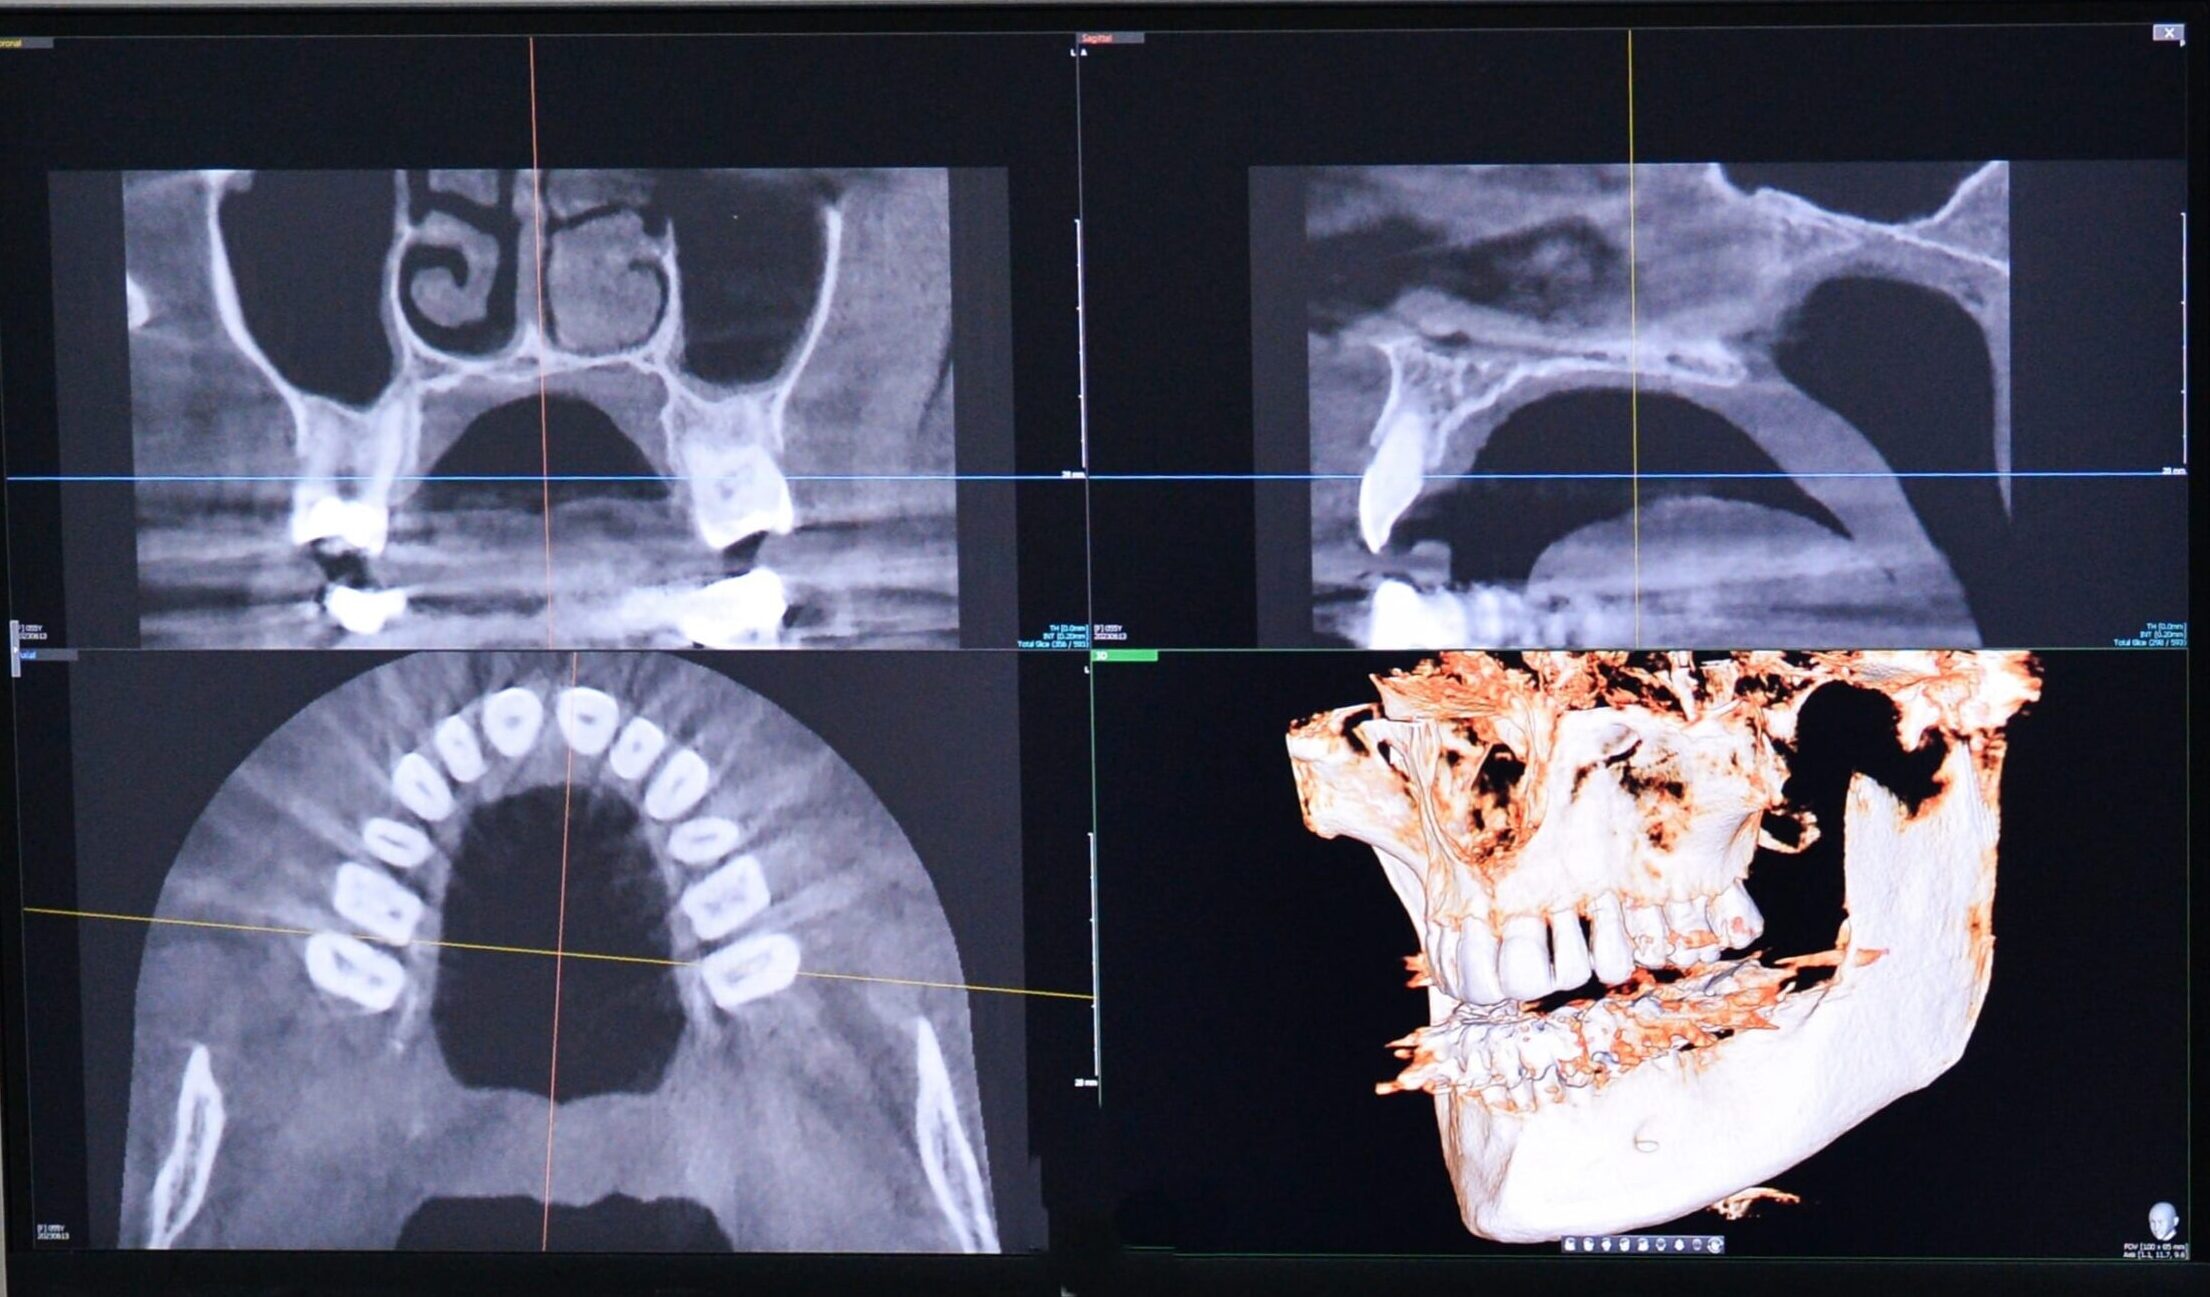

3D snimanje zuba, ili CBCT (Cone Beam Computed Tomography), pruža trodimenzionalnu sliku zuba i vilice, omogućavajući detaljan uvid u strukturu zubnog aparata. Ova tehnologija koristi specijalne senzore i računalne algoritme kako bi stvorila kompletnu trodimenzionalnu sliku koja se može rotirati i detaljno analizirati. Za razliku od 2D snimanja, 3D snimanje omogućava stomatolozima da procene i najmanje detalje zubne anatomije, uključujući korene, živce i okolne kosti. Zbog svoje preciznosti, 3D snimanje postaje sve češći izbor za složene stomatološke tretmane.

- Precizna dijagnostika: 3D snimak omogućava stomatolozima da precizno analiziraju strukture zuba, korenova i vilice, što je od izuzetne važnosti za tačne dijagnoze.

- Detaljna vizualizacija: Omogućava slojevito prikazivanje kostiju i tkiva, što je posebno korisno kod složenih problema i za planiranje kompleksnih zahvata.

- Planiranje tretmana: Ova vrsta snimanja je nezamenjiva kod planiranja zahvata kao što su zubni implantati, ortodoncija i hirurške intervencije.

- 3D snimak omogućava trodimenzionalnu vizualizaciju, što znači da stomatolog može videti sve slojeve i detalje iz različitih uglova, što je ključno za preciznu dijagnozu.

- 3D snimak daje vrlo visoku preciznost i detaljnost, omogućavajući stomatologu da sagleda svaki sloj zubnog i koštanog tkiva, uključujući korene i kanale, što je od presudne važnosti kod složenih dijagnoza.

- 3D snimanje je idealno za složene procedure kao što su ugradnja implantata, ortodontska procena položaja zuba ili hirurške intervencije na vilici, gde je preciznost presudna.

3D snimanje se koristi kada su potrebne precizne informacije o unutrašnjoj strukturi zuba i vilice. Na primer, pri planiranju implantata stomatolog koristi 3D snimak kako bi precizno odredio položaj i stanje kosti, što je od suštinske važnosti za uspešnu ugradnju implantata. U ortodonciji, 3D snimak omogućava detaljno sagledavanje položaja zuba, što pomaže u planiranju tretmana i proceni trajanja terapije. Hirurške intervencije, kao što su uklanjanje komplikovanih cisti ili tumora, takođe zahtevaju 3D snimanje zbog kompleksnosti struktura i preciznosti koju pruža ova tehnologija.